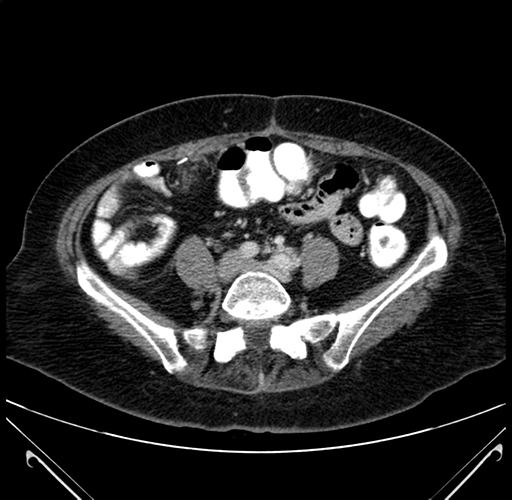

Pre-Chemo: Axial Venous

Axial Venous